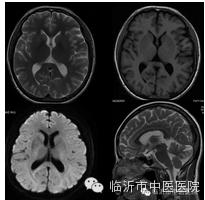

对颅脑组织的对比度增加,能更清晰的显示解剖结构和病变组织,尤其DWI成像使得对病变组织的显示更敏感。

常用于超急性脑梗塞的诊断与鉴别诊断,有利于尽早挽救可逆性缺血性坏死脑组织,对于指导临床治疗具有重要的意义。